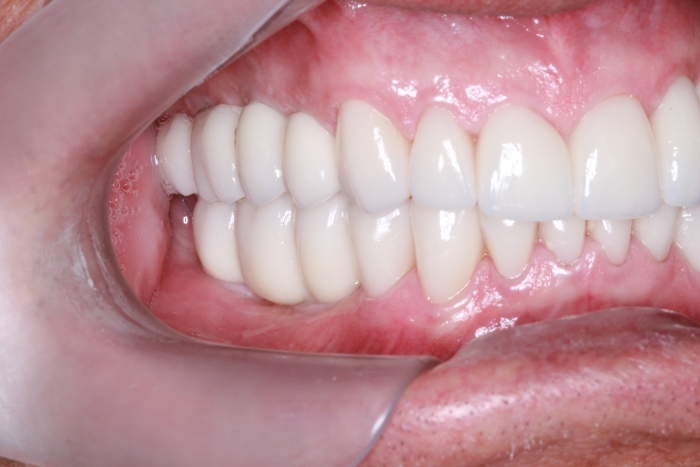

Intra oral direita final